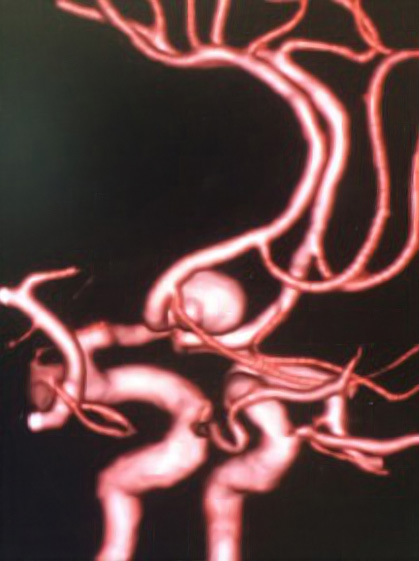

海綿静脈洞部巨大動脈瘤に対しCAS抜去後にhigh flow bypass+内頸動脈近位遮断を行なった症例

左内頸動脈海綿静脈洞部の巨大動脈瘤の患者様です。他院で血管内治療を行なった際に解離が起き、内頸動脈から総頸動脈にステントが留置されており、当院での治療を希望され来院されました。浅側頭動脈ー中大脳動脈バイパスを行なった後、頸部で内膜剥離術を行いstentを抜去し外頸動脈から中大脳動脈にバイパスを作成し、内頸動脈近位部で結紮遮断しています。CAS後でエフィエントを休薬せずに開頭手術を行ったため止血操作に時間を要しましたが合併症なく自宅退院されています。

- A: 術前面像ですが左内頸動脈に瘤を認めます。

- B: 頸部内頸動脈にステントが留置されています。

- C: 術中所見ですがステントをCEAにより剥離除去できました。

- D: high flow bypassとSTA-bypass後に内頸動脈を遮断しています。

- E: 術後一過性に静脈還流障害を認めましたが回復しております。